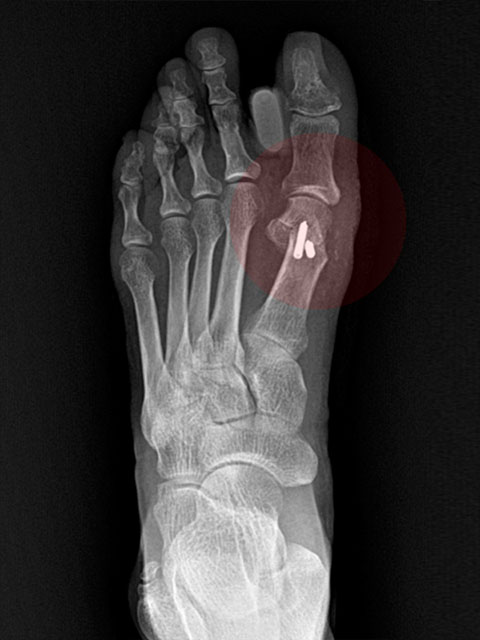

2cm

무지외반증

교정술 사례

-

Before

엄지발가락이 둘째 발가락 쪽으로 심하게 휘어 관절의 탈구가 우려되는 단계

After

심하게 꺾였던 엄지발가락의 각도가 수술 후 일자로 교정된 상태